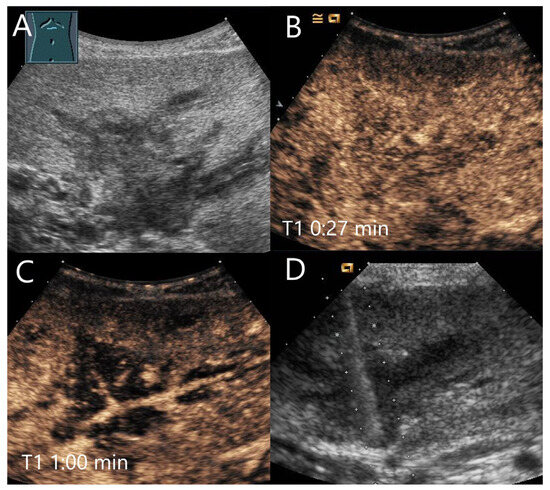

Figure 2.

Partially fibrosed hemangioma. As part of a staging examination for adenocarcinoma of the gastro-esophageal junction, a 19 mm, smoothly bordered hyperechoic lesion (arrow) with an implied hypoechoic rim and punctate echogenic reflexes is diagnosed in the liver (A). On CEUS, the small lesion (between the markings) shows a marginal contrast image that is not completely smooth (B). In the PVP after 1:25 min, most of the lesion is enhanced, but slightly less than the surrounding parenchyma and with a small portion that is clearly hypoenhanced (C). After 3:04 min, the lesion is slightly hypoenhanced (D), while after 4:22 min (E) and 6:08 min (F), the lesion shows an unequivocal hypoenhancement. The lesion did not clearly correspond to a hemangioma on computed tomography either. This was the reason for a US-guided biopsy. Histology revealed a hemangioma, partially fibrosed and with tiny calcifications.